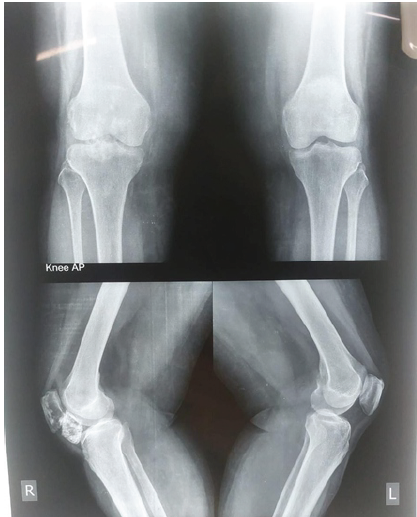

A 65-year-old female presented to the orthopedic outpatient department with a chief complaint of right knee pain and swelling that had progressively worsened over the last year. The pain was described as a dull ache, exacerbated by activity and partially relieved by rest. In addition, the patient experienced mechanical symptoms impacting her mobility and quality of life. No significant past medical history. No history of trauma to the knee. No family history of bone tumors or hereditary multiple exostoses. Physical Examination revealed a visible swelling on the inferior aspect of the right knee, a firm, non-tender, immobile mass. Range of motion was limited, particularly in flexion. Neurovascular status of the limb was intact. Initial anteroposterior and lateral knee X-rays showed a well-defined, bony outgrowth from the inferior aspect of the patella (Fig. 1).

Figure 1: Pre-operative X-ray.